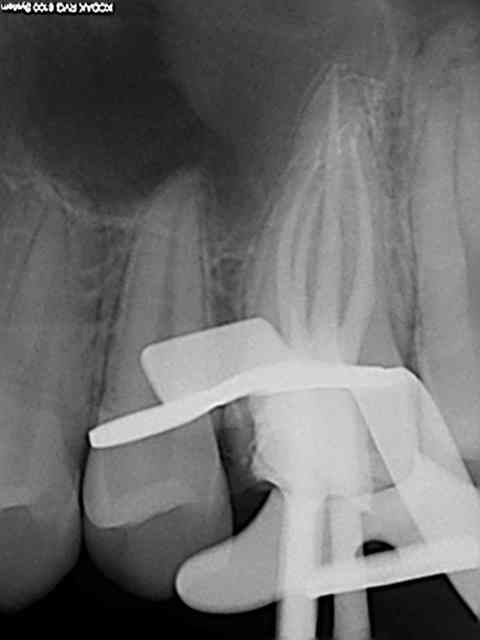

21/02/2014 à 01h10

On voit mieux ici cone en place.